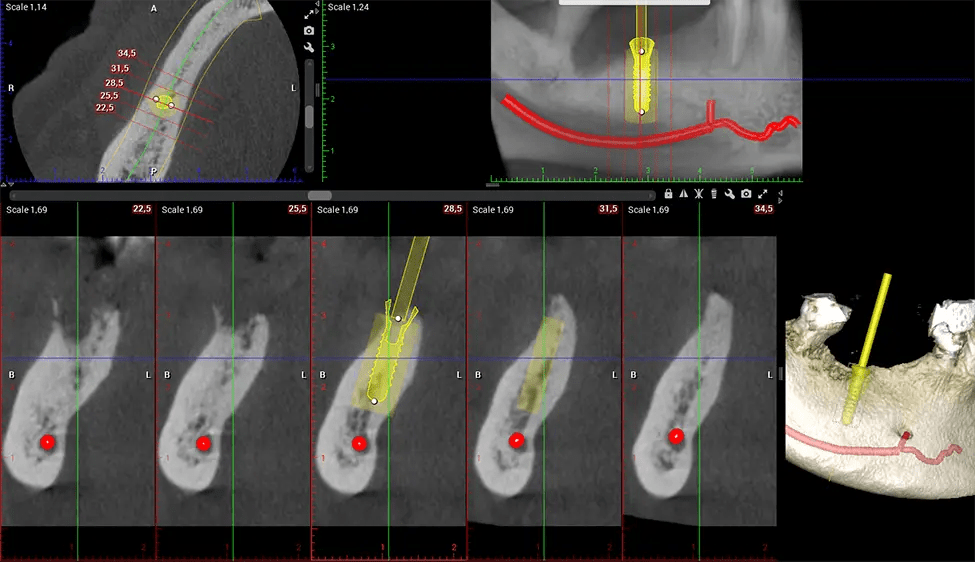

Oral and Maxillofacial Surgeon Complex oral surgeries, orthognathic (jaw) surgery, and removal of impacted teeth. Offers precise, three-dimensional visualization of the skull, jaw, and craniocervical junction to enhance diagnostic accuracy and minimize surgical risks.

When paired with extractions, dental implant placement, or bone grafting, CBCT technology can provide you with a quicker and much more comfortable experience. This is because the 3D image provides a more detailed picture of your entire oral cavity, allowing your dentist to walk you through each step of the process before it occurs. This often helps patients feel more prepared and comfortable overall, especially if they have had a traumatic experience with past dental treatments.

After the scanning process, the captured X-ray images are processed by the CBCT software, which applies algorithms to reconstruct a detailed 3D image of the scanned area. The software compiles these individual X-ray images and creates a digital 3D representation of the patient’s anatomy. The reconstructed 3D CBCT image can be viewed and analyzed by the dentist or radiologist. This image can be manipulated, rotated, and zoomed in or out to examine specific structures and evaluate the patient’s condition.